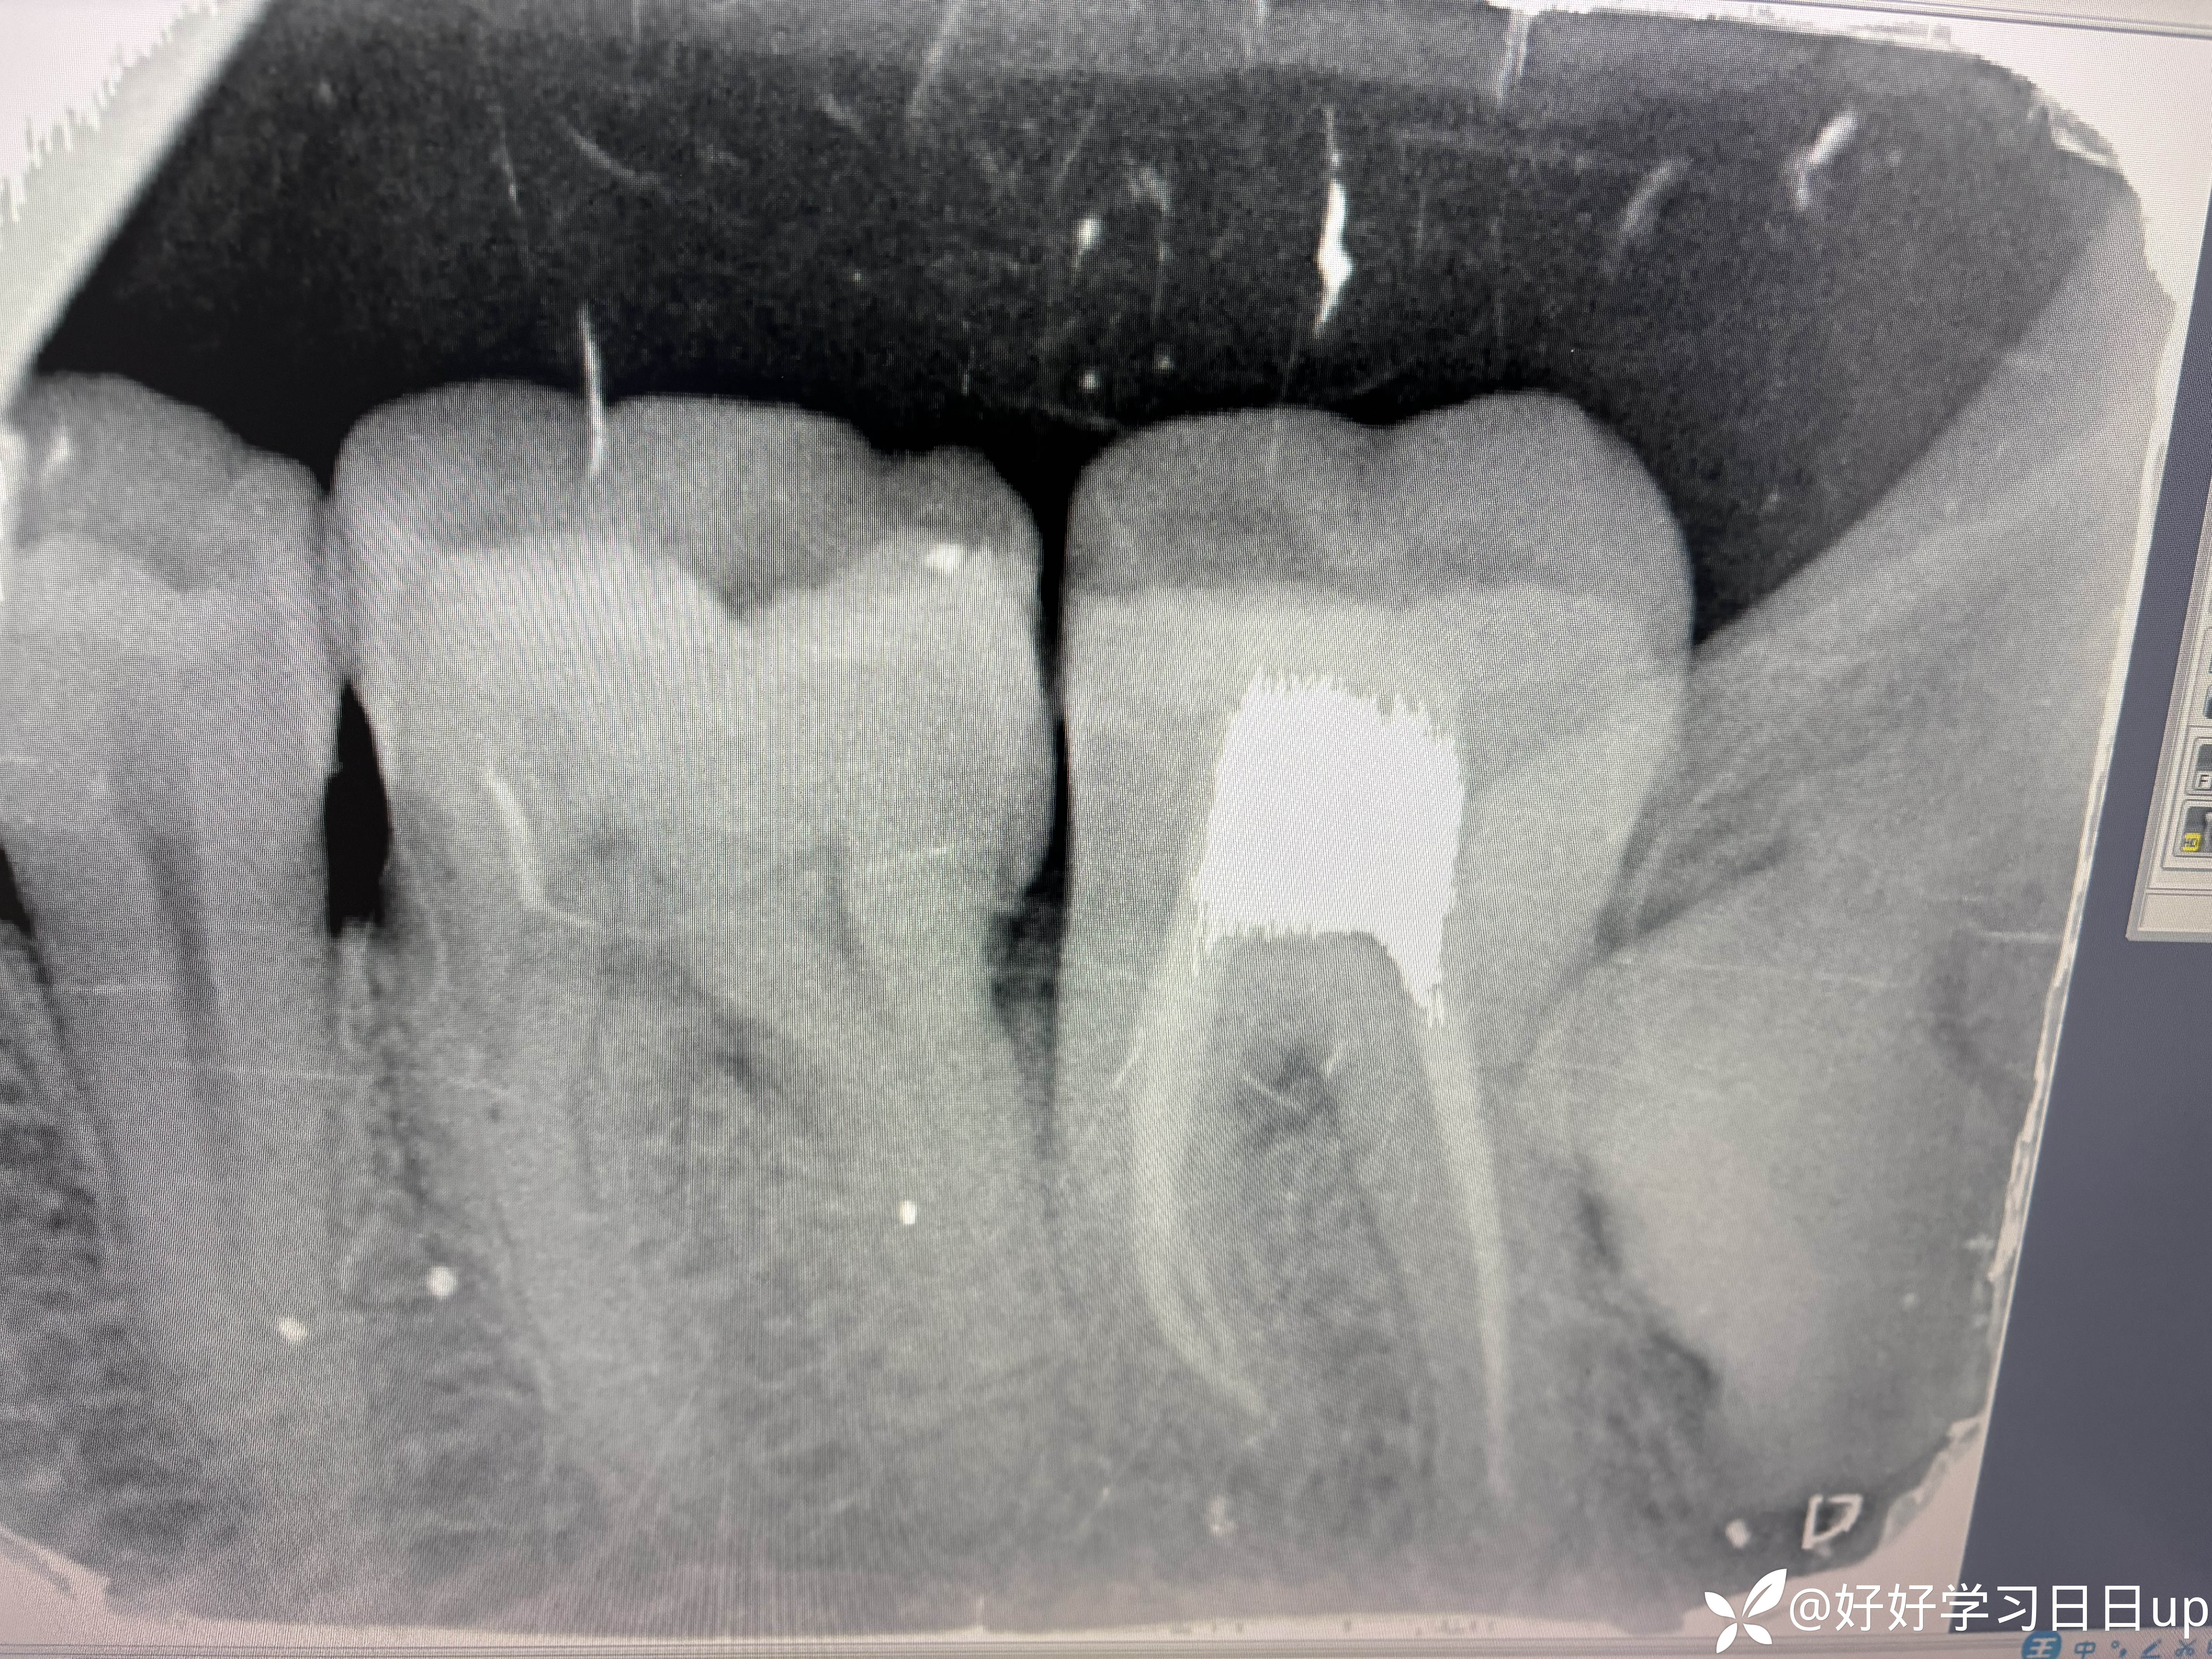

今天来了说肿了补的位置牙线用的过程中掉了一块,口内看可能是牙周脓肿,于是拍了一张根尖片,感觉不是根管引起的瘘管,引流脓液,洁治后,发现近中缺损部位疑似隐裂,拆除充填体发现隐裂贯穿近远中但是裂的位置卡不进探针,再次向下打磨隐裂部位,本来想完全去除隐裂,但没想到裂的还是比较深害怕抗力越来越差,跟患者说可能需要拔除,或者降低咬合后续观察,患者选择降低

我当时的想法是做一个树脂嵌体,但是想想好像也没作用,直接流体填起来降低到咬不到,颌面流体颊舌向做了一道杠想着给牙一个像中心的力量(瞎搞的也是没招了),老师们遇见这种是直接建议拔除还是有其他方法?是隐裂引起的脓包吗?